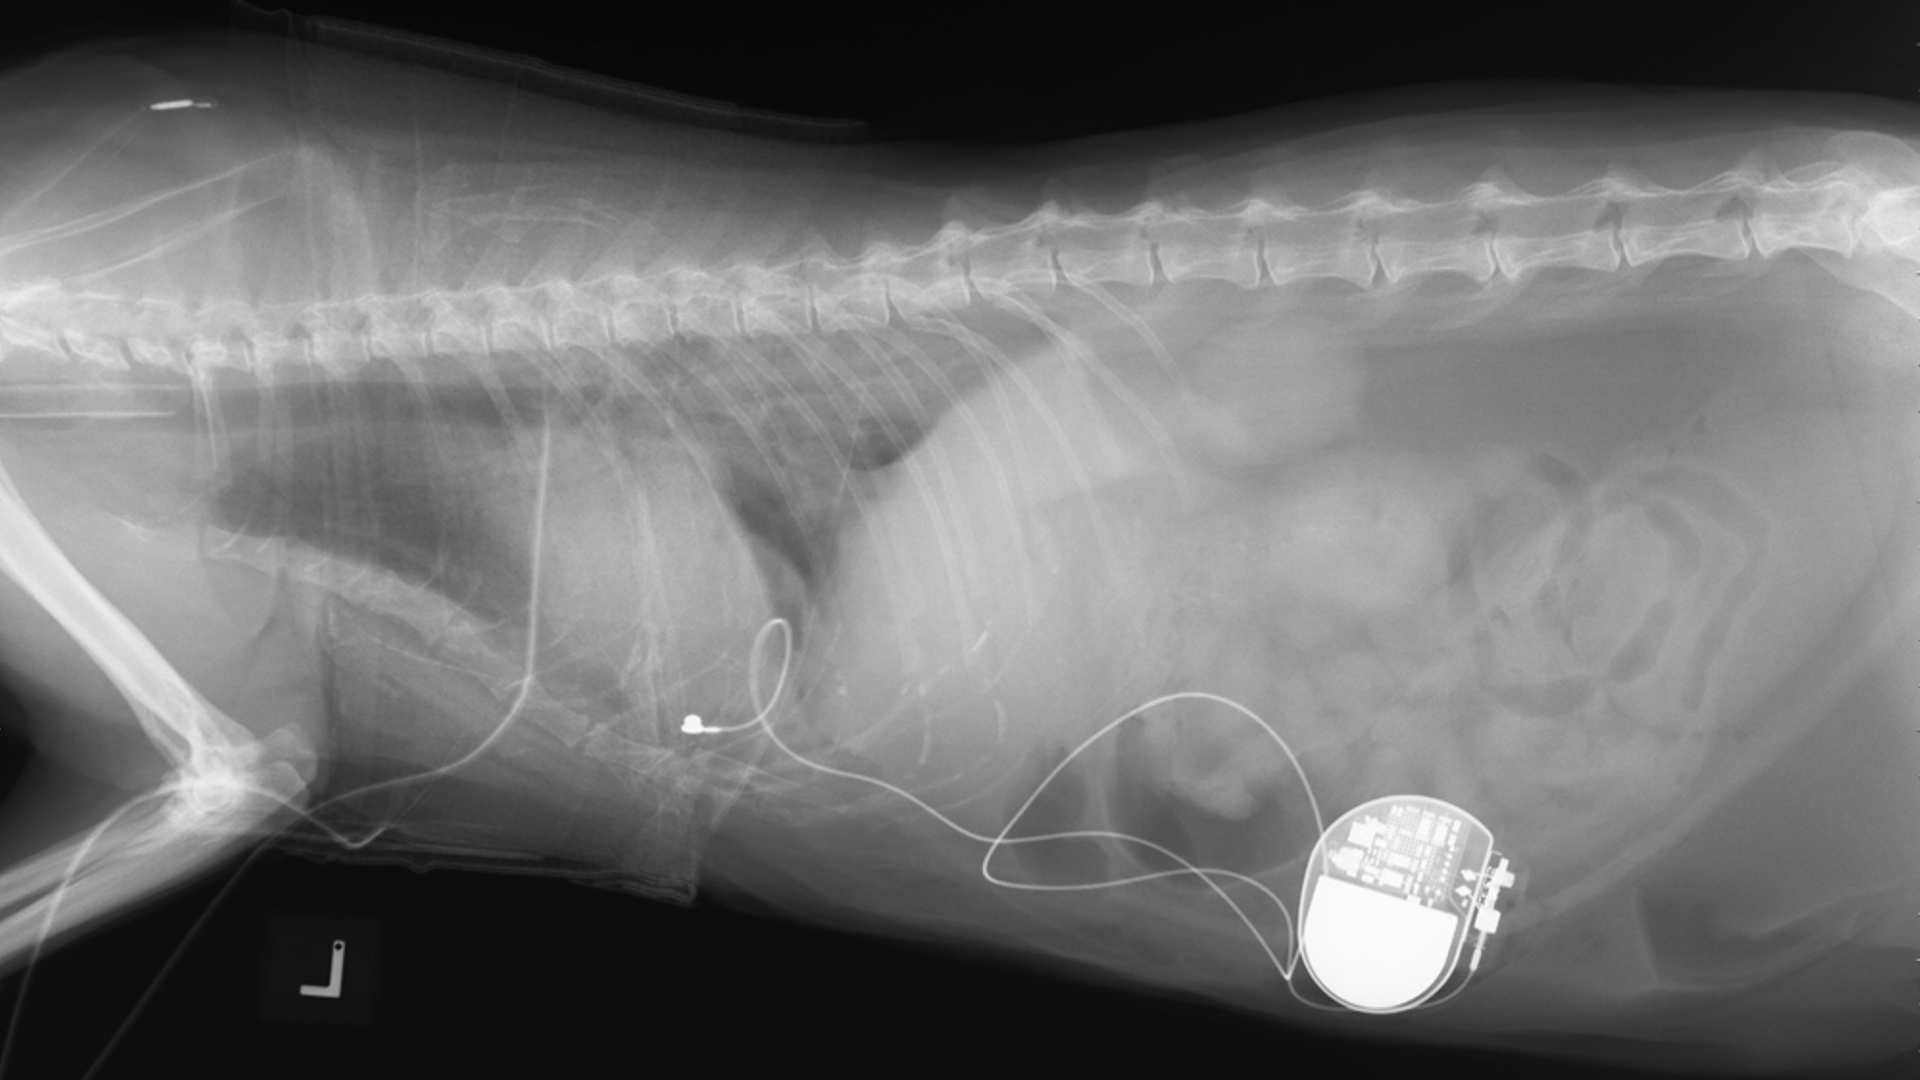

Phoenix and Merlin - Feline Pacemaker

Phoenix and Merlin both presented to Langford Vets Cardiology Service within 24 hours of each other in December 2023 for investigations of collapse episodes.